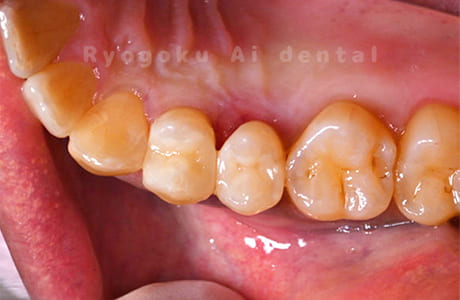

- 治療内容

- 24番ダイレクトボンディング、25番セラミックインレー修復、26・27番セラミッククラウン修復

- 387,000円

歯がしみるとのことでご来院された患者様です。銀歯の中が大きく虫歯になっておりました。セラミックの材料で再治療を行いました。